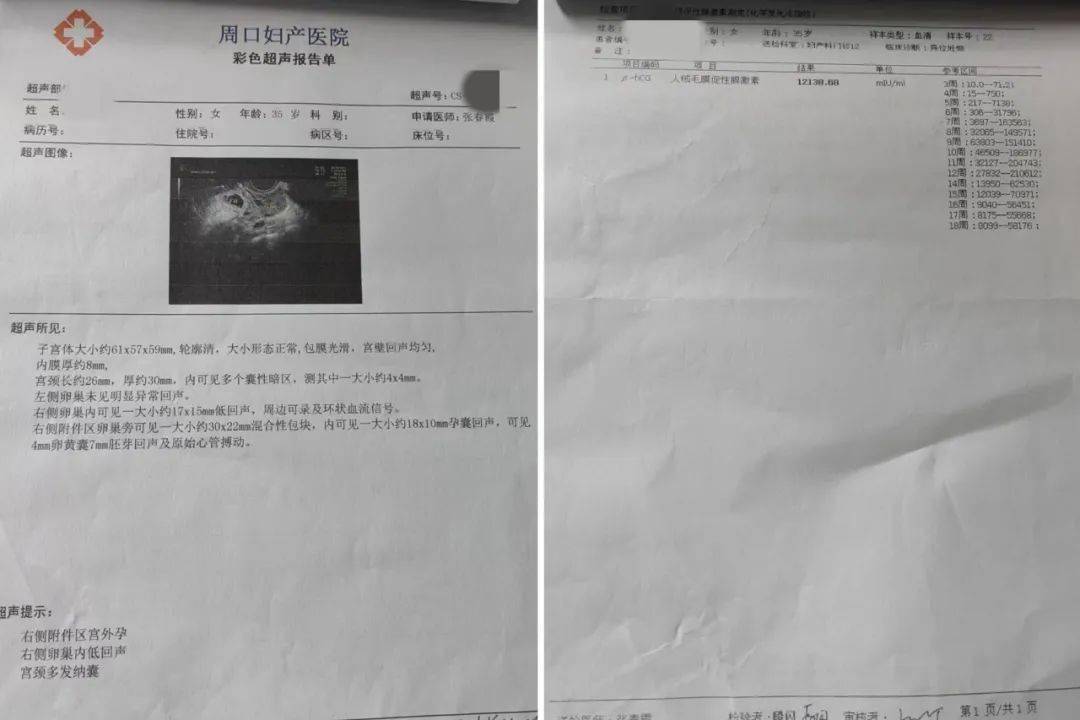

阴道异常流血伴腹痛,竟然是宫外孕?_周口_输卵管_陈女士

图片尺寸1080x720